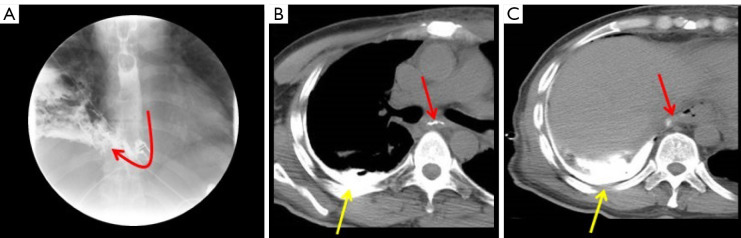

Abstract Image